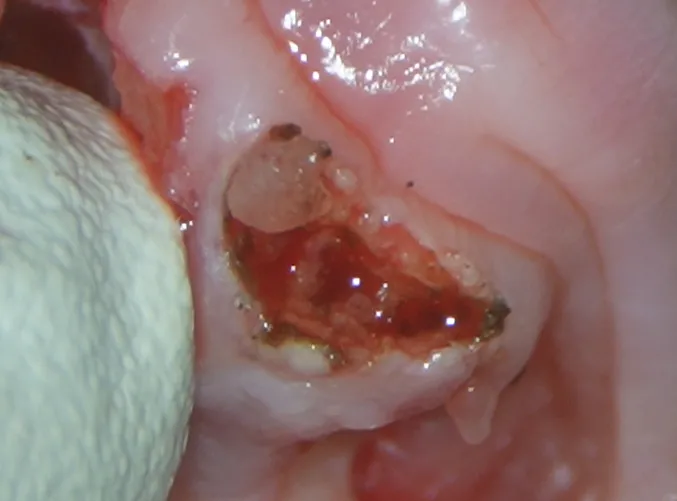

処置中

内科療法では改善が乏しかったため、麻酔をかけ全ての歯の抜歯をおこないました。

小さくて見えにくかった小さな歯もマイクロスコープにより認識しやすくなりました。

処置後は内科療法を継続し、1年後には炎症もだいぶ引いたのが分かります。